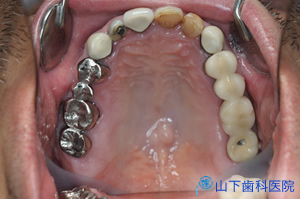

| こうして埋入した6本のSpeedy インプラントにストレートのマルチユニットアバットメントを付けた状態です。 この写真は縫合部が治癒し、組織外に残る糸を取った時の写真。 |

| 1度にインプラント体6本を埋入して仮の上部構造体まで装着したところです。 | ![]() |

| そのオルソパントモレントゲン像です。 順調にいけば、およそ4か月でインプラント体が骨と結合します。仮の上部構造体で分かった注意点、改善点を盛り込み、よりしっかりした材質で機能的にも審美的にも満足のいく最終上部構造体を作り直す、これが大型のインプラント修復の標準治療の流れです。 |

![]() |